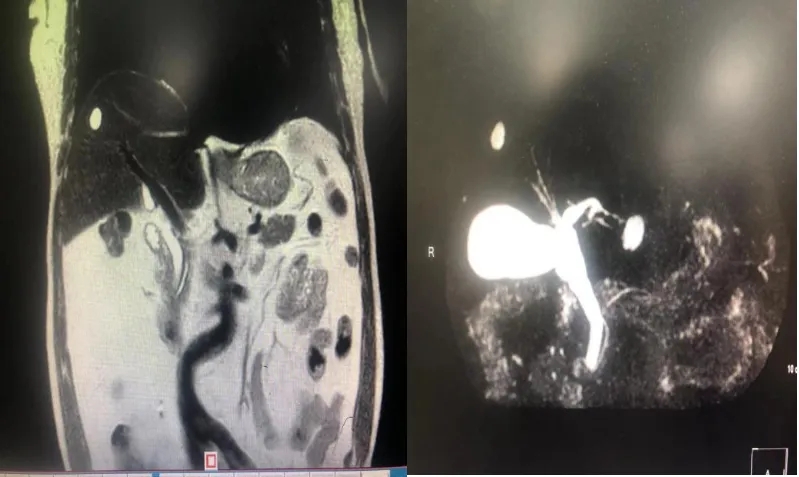

1月14号,肝胆腺体周围血管病外科收到2位患者赠送的锦旗,其中一面锦旗更是用了一个非常简单、接地气的“牛牛牛”“靠谱”“YYDS”等字眼表达了对韦...